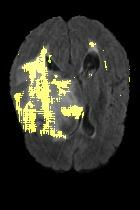

Current unsupervised anomaly localization approaches rely on generative models to learn the distribution of normal images, which is later used to identify potential anomalous regions derived from errors on the reconstructed images. However, a main limitation of nearly all prior literature is the need of employing anomalous images to set a class-specific threshold to locate the anomalies. This limits their usability in realistic scenarios, where only normal data is typically accessible. Despite this major drawback, only a handful of works have addressed this limitation, by integrating supervision on attention maps during training. In this work, we propose a novel formulation that does not require accessing images with abnormalities to define the threshold. Furthermore, and in contrast to very recent work, the proposed constraint is formulated in a more principled manner, leveraging well-known knowledge in constrained optimization. In particular, the equality constraint on the attention maps in prior work is replaced by an inequality constraint, which allows more flexibility. In addition, to address the limitations of penalty-based functions we employ an extension of the popular log-barrier methods to handle the constraint. Comprehensive experiments on the popular BRATS'19 dataset demonstrate that the proposed approach substantially outperforms relevant literature, establishing new state-of-the-art results for unsupervised lesion segmentation.